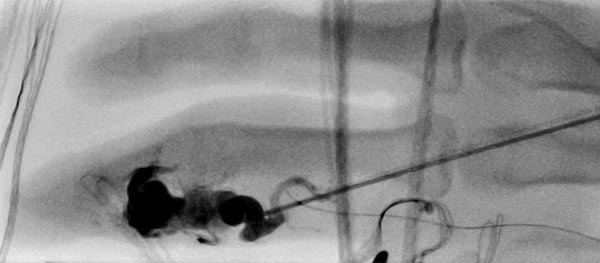

The nidus of the AVM in a magnified target image of the D III in digital subtraction angiography shows significant increase in size compared to the old angiographies (not shown). DSA images after transarterial antegrade puncture of the brachial artery with hypervascularized AVM of the middle and distal phalanx.

Fluoroscopic view of the puncture needle at the start of direct percutaneous embolization therapy of the finger with a liquid embolic agent (EVOH). The microcatheter which has been advanced to the nidus is additionally visible.

Fluoroscopic control after successful nidus embolization of the AVM. The transarterially inserted microcatheter was left in place during percutaneous embolization as a landmark for the feeding digitalis propria artery. In addition, radiopaque markers are displayed by gauze placed on the skin.